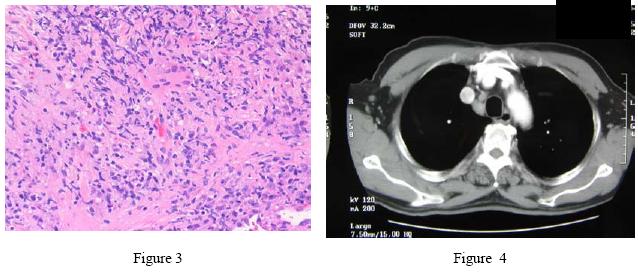

The sputum for AFB smears was negative on two occasions. Fibro-optic bronchoscopy (FOB) was performed on 28/6/2005; there was no endobronchial lesion and bronchial aspirate for AFB smear & culture were negative. Transbronchial biopsy from apical segment of RLL showed infiltration of lymphocytes, plasma cells and multinucleated giant cells, non-caseating granulomatous inflammation and fibrosis. The PCR for MTB DNA was however negative (Figure 3). Out-patient CT thorax and abdomen on 14/7/2005 confirmed no other mass lesion in both lungs. The abnormal findings included multiple enlarged lymph nodes in the pre-carinal, right paratracheal and bilateral hilar regions as well as striated enhancement pattern in both kidneys (Figure 4). He was referred to our respiratory clinic for follow up by our geriatric colleague but he defaulted again.

The submandibular glands enlargement persisted and he later developed episcleritis over the left eye. HRCT thorax on 18/10/2005 showed smooth septal thickening in both upper lobes, multiple tiny nodules with upper lobe predominance. Many were subpleurally located and ran along the fissures. The enlarged nodes still persisted over bilateral hilar & paratracheal region (Figure 5). Lung function test had been attempted for 16 times but all failed. A second FOB was repeated on 19/10/2005. It showed no endobronchial lesion. Biopsy from posterior segment of RUL & apical segment of RLL revealed fragments of lung tissue only, with focal fibrosis and scanty histiocytes. The cultures of bronchial aspirate were negative for bacteria, AFB & fungus. Renal biopsy was subsequently performed on 21/10/2005. It revealed the pathological diagnosis of non-granulomatous interstitial nephritis (Figure 6). Anti-nuclear factor screening was positive and the titre was 1:160. Other relevant investigations included HBsAg, Anti-HCV antibody, cryoglobulin, HIV, VDRL, ANCA , dsDNA and ENA , serum protein electrophoresis and urine BJP were all negative. A working diagnosis of sarcoidosis was thus fully established in view of the clinical, radiological and histological findings. Further investigations including Mantoux test (MT) 2, urine culture, urine for AFB culture, serum cryptococcal Ag, galactomannon, brucella antibody, toxoplasma antibody were negative subsequently. The serum lysozyme was elevated to 1771 u/ml (normal range: 150-500u/ml) but the serum angiotensin converting enzyme level was normal.